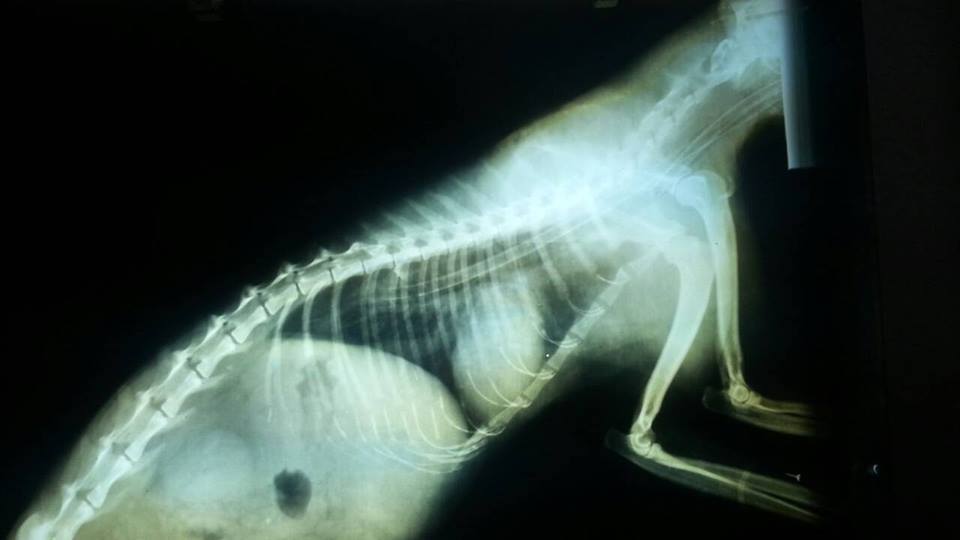

主題: 口炎完全不進食老貓 申請者姓名: 陳曉霏 花色: 申請日期: 2014-08-14 19:23:22 申請者部落格: 申請者臉書網址: 所在縣市/合作醫院: 台北市/澄毅動物醫院 治療費用: 10320元 需求人數: 24人 已結案 (2014-09-04 10:07:00) 報名人員: Mark Hsu x2(已付款)、Furby Lin、may(已付款)、may(已付款)、may(已付款)、may(已付款)、Pinion x2(已付款)、Way Chen(已付款)、泰合資訊管理股份有限公司 x2(已付款)、みやびしゅう x2(已付款)、fang7880(已付款)、綠袖、綠袖(已付款)、陳曉霏 x2(已付款)、陳曉霏 x5(已付款)、Bonnie Liu(已付款)、吳雅惠(已付款)、 候補人員: Emily(已付款)、 動物病情說明: 在外面生活的貓

長期受口炎所苦

疼痛時 完全無法進食

稍微不疼食 或許能多少吃一點

這孩子 年記很大了

不知他口炎多久了

也不知他不舒服多久了

誘補他時 他已經完全不進食了

雖然很困難 但還是能順利帶他進醫院

但是他已經沒力氣了

他雖然不喜歡 但是也沒力氣反抗了

他脫水的嚴重 牙齦沒有血色

雖然已經上了點滴

但他還是不願意吃

最後不得以 只能幫他插食道胃管

或許是在外流浪的生活太辛苦

或是是我太晚救到他

所以他沒有求生意志

在醫院他出現了癲癇還有失溫

最後他還是選擇離開了

但還好 不是讓他孤單單在外面渡過

懇請大家幫忙最後一程的費用 感謝!